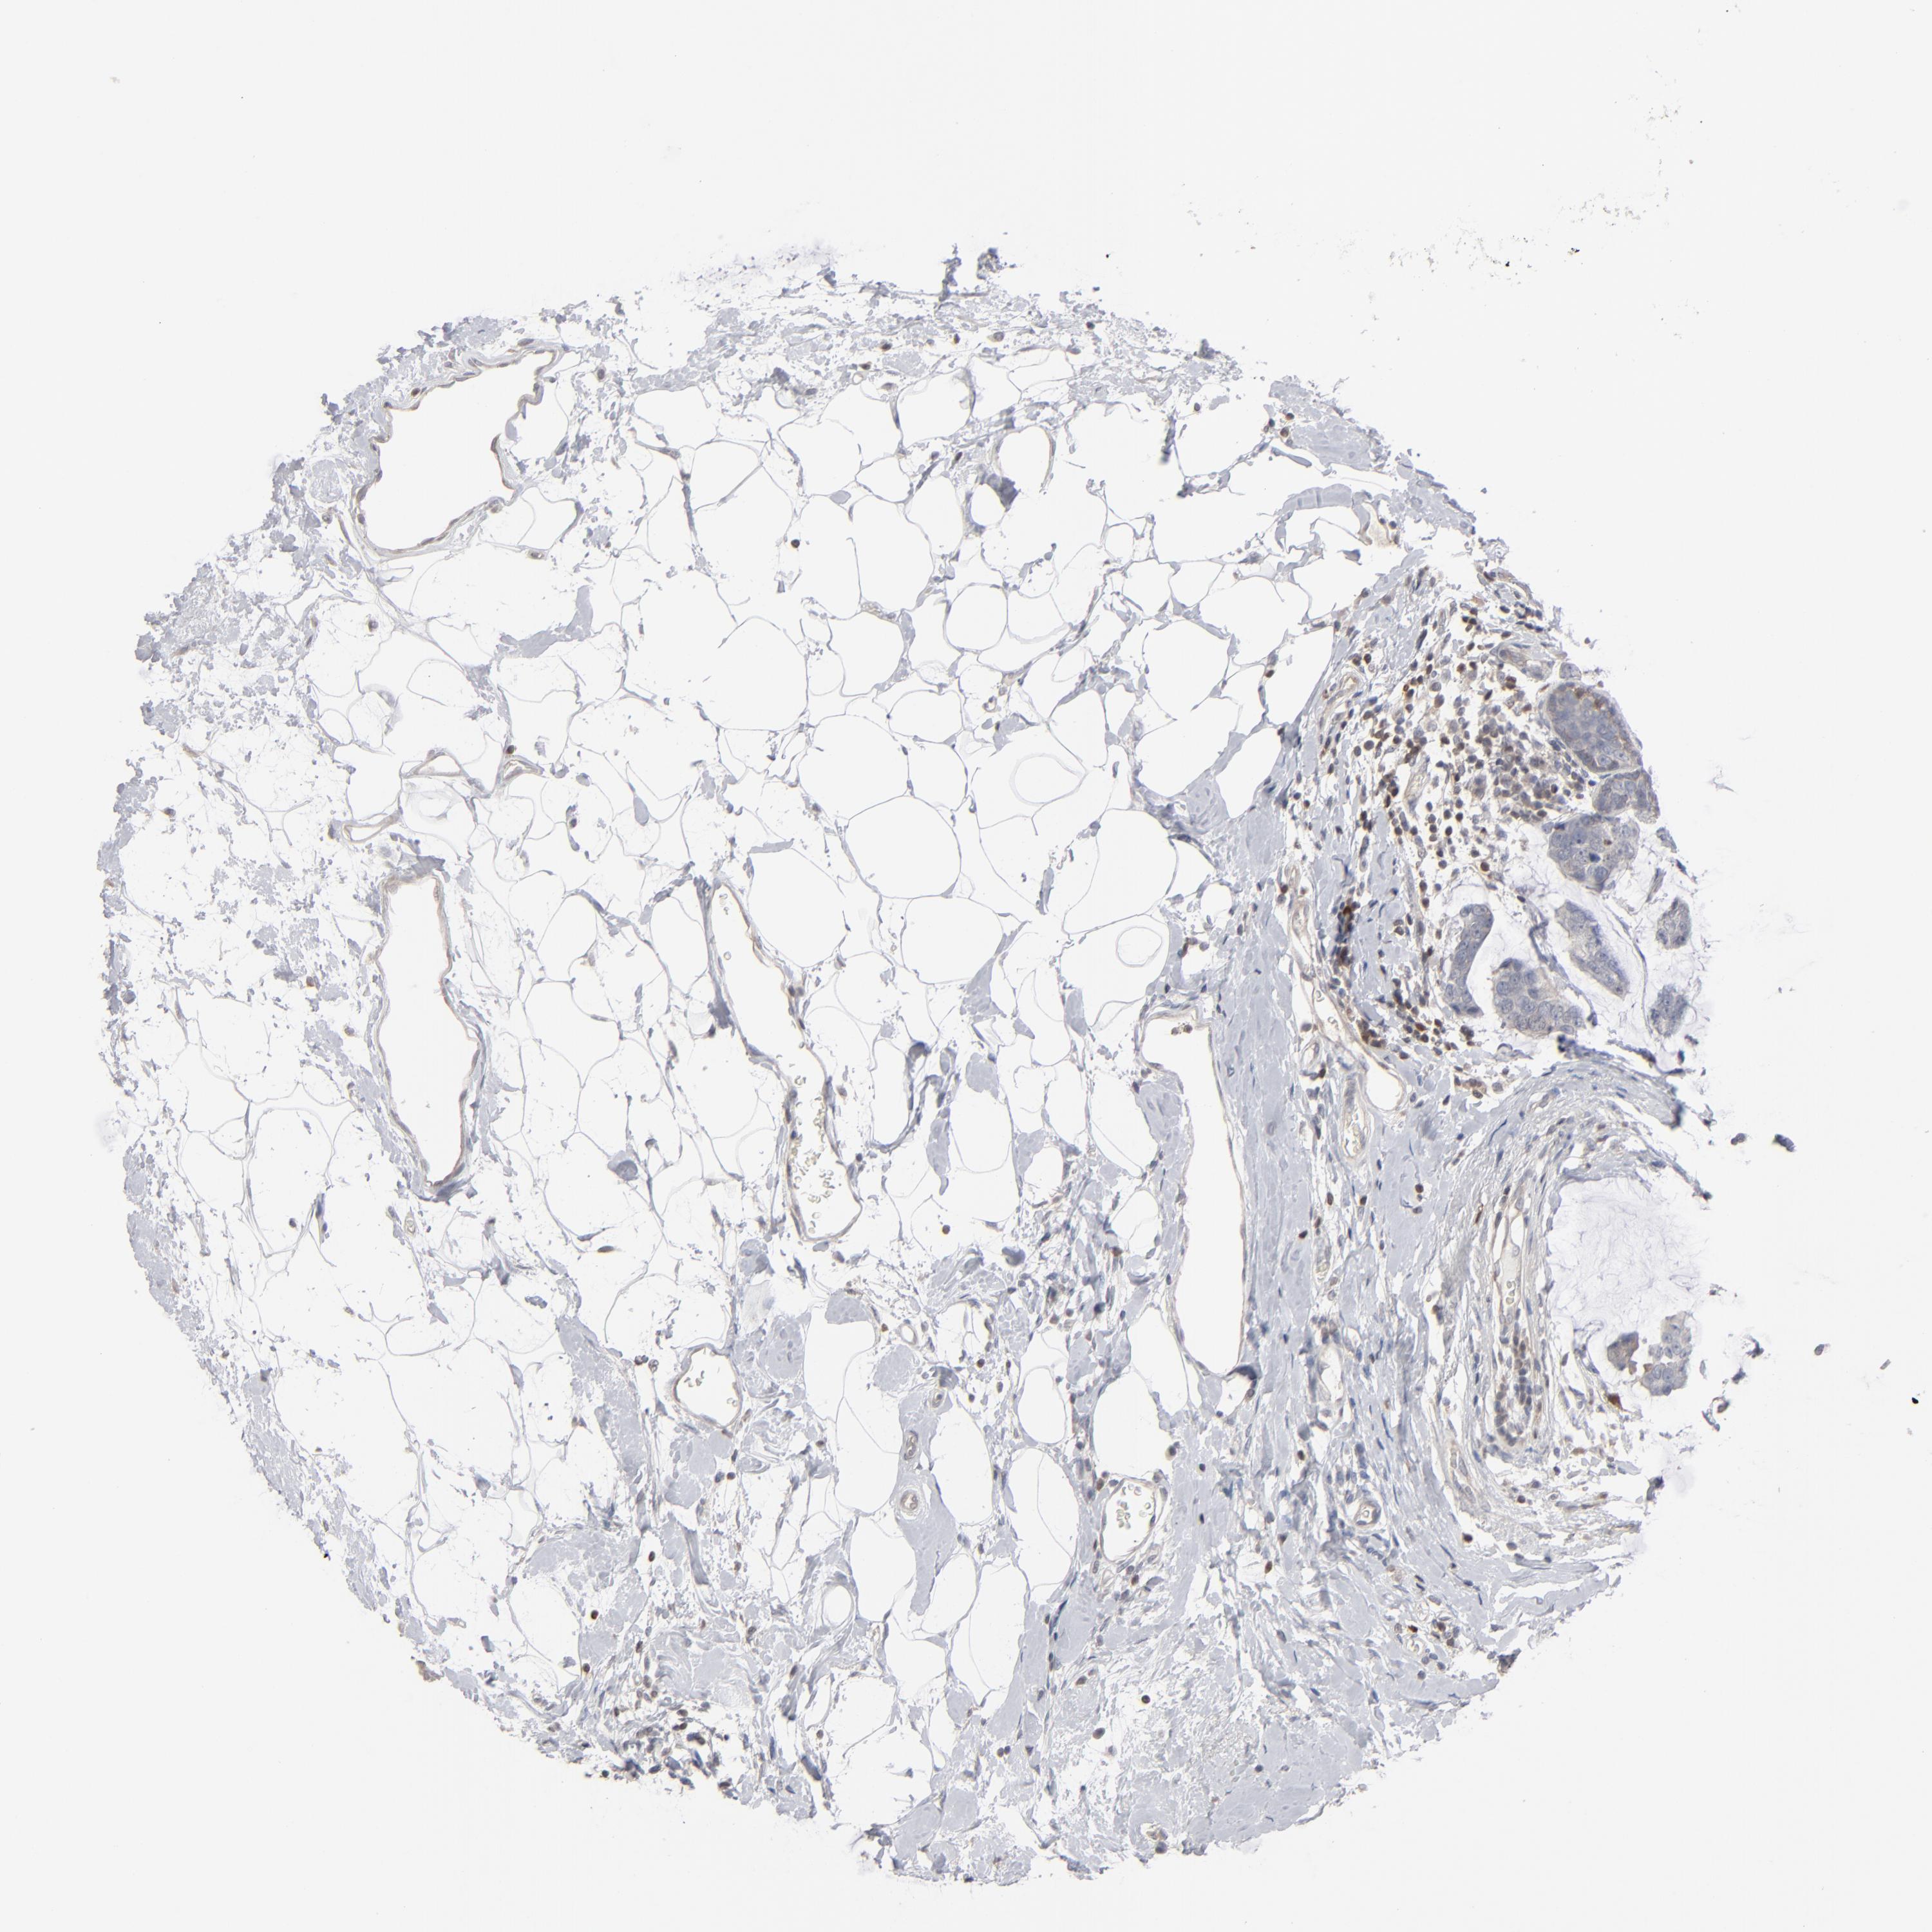

CANCER BREAST CANCER Show tissue menu

BRCA TCGA BRCA VALIDATION PROTEIN EXPRESSION